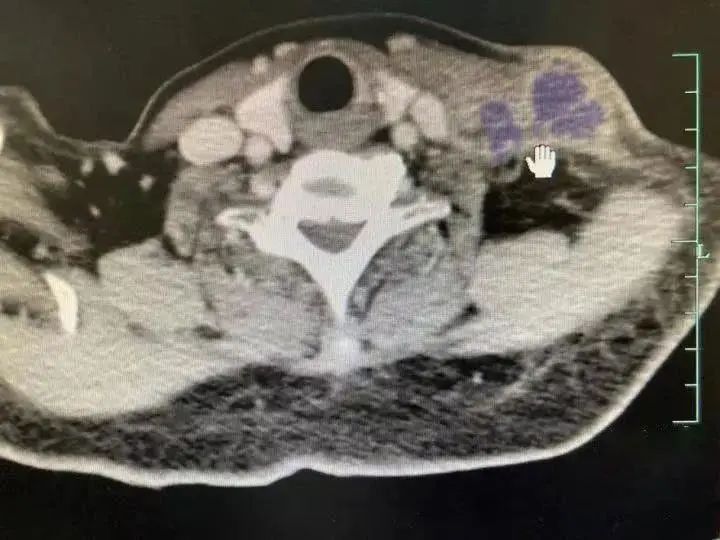

两个月前,毛宇突然出现头痛、头晕、颈部酸痛、发热、咳嗽等症状。自己服用感冒药后,他去了当地的县医院。但经过9天的住院治疗,他反复发烧,体温高达40℃,出现视力下降、右眼视力不足等症状。

病人右眼眼底照片

有些病人会出现眼部疾病,如视盘水肿、黄斑水肿伴渗出,然后逐渐形成黄斑前膜等,导致视力下降。